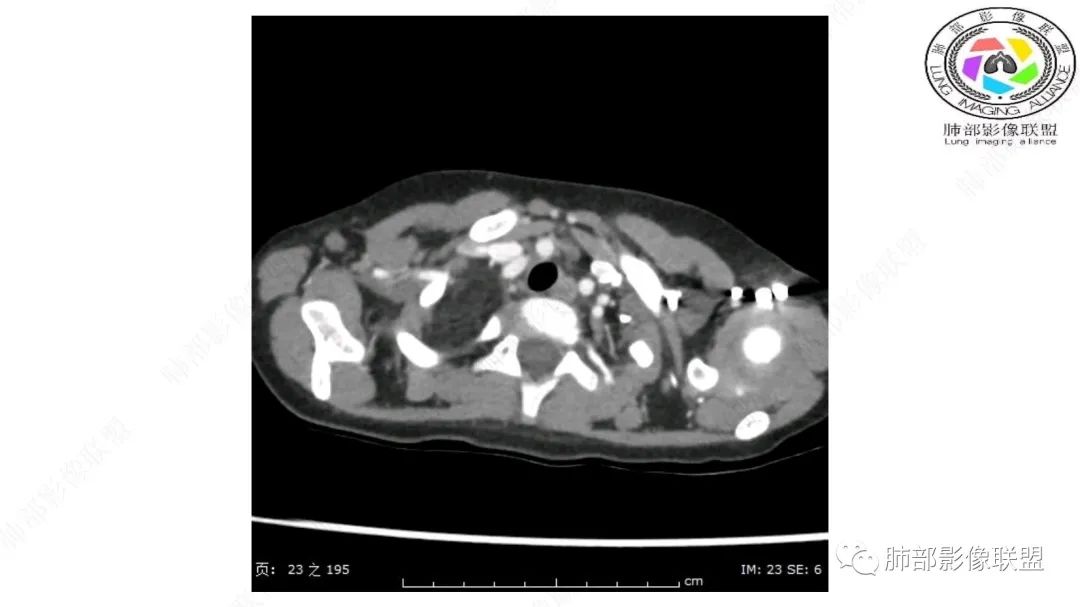

右上纵隔混杂密度肿块,边缘光整,与纵隔分界清,其内多发脂肪密度,增强无明显强化,其内血管穿行,考虑纵隔脂肪母细胞瘤,鉴别畸胎瘤,脂肪肉瘤。

3岁儿童,右纵隔占位,内部间多发脂质成分及斑片状稍高密度影,考虑纤维成分,增强似有强化。病灶内血管未见明显侵犯,可考虑脂肪母细胞瘤,冬眠瘤等。

三岁小儿,右侧纵隔巨大脂肪密度肿块,肺动脉穿行其中,密度欠均匀,未见明确实性成分,纵隔脂肪母细胞瘤,冬眠瘤鉴别纵隔脂肪增多症(多弥漫对称)。

幼儿,右上纵膈团块,脂肪密度,内见分隔,增强病灶内见血管穿行,结合患者年龄,考虑脂肪母细胞瘤,鉴别脂肪瘤。

跨肺门,包绕肺血管分支,邻近肺组织受压肺不张。

可以看到造影剂进入的丛状结构

密度不均,非纯脂肪成分。斑片状密度略高区域有轻度填充式强化。

婴幼儿,病变较大,跨肺门,分叶,富含纤维或黏液、含成熟脂肪,破坏力弱或无,浸润性生长模式不明显,未见远处转移。

病灶属于交界区,主体位于肺内,占位效应明显,前方突入胸壁,胸腺受压变形,胸膜显示欠清楚;病灶包绕上叶肺动脉;似乎有体动脉供血。符合肺内的点:包绕上叶肺动脉分支;符合纵隔的点:前方似乎突入胸壁,与胸腺关系比较密切,但是与上腔静脉的关系提示病灶不支持纵隔来源,前纵隔的常规会将上腔静脉受压后移、外移,这是不符合的。

2.肺动脉穿行也许是肺内来源最重要支持点!

脂肪母细胞瘤由成熟程度不同的脂肪组织、纤维间隔、黏液基质、小血管丛等间质成分组成,以脂肪组织与黏液样基质为主,其影像学表现取决于上述组织成分。典型的CT和MRI表现为:前后纵隔均可发生,常见于前纵隔;肿块大小不一,直径多在3cm~7cm,密度均匀,CT值呈水样或脂肪密度,脂肪组织密度或信号为主的肿块,其内密度或信号不均匀,可见粗细不一的分隔影,且有结节、片状影,后者可呈轻中度强化;结节状肿瘤包膜完整;弥漫性者包膜不明显,常呈浸润性生长;周围结构为受压和推移改变,可有少量胸腔积液,淋巴结无增大。